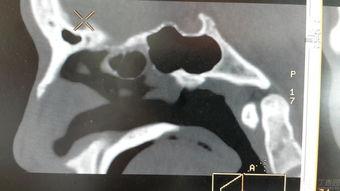

二、鼻骨塌陷的图片,让你大吃一惊!

1. 自然美鼻骨塌陷图片

在网络上,我们可以找到很多自然美鼻骨塌陷的图片。这些图片展示了鼻骨塌陷者在日常生活中真实的样子,让人不禁感叹大自然的神奇。

3. 鼻骨塌陷修复前后对比图片

当然,鼻骨塌陷并不是不可改变的。通过整形手术,许多鼻骨塌陷者成功改善了鼻型。这些修复前后的对比图片,让人看到了改变的奇迹。